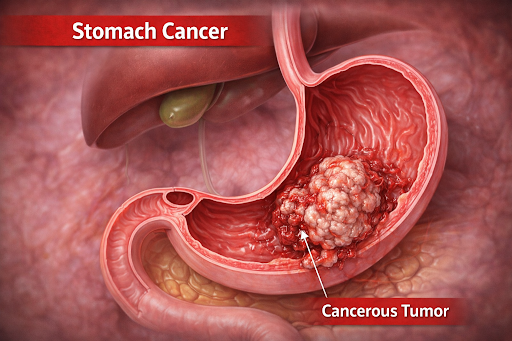

Overview of Stomach Cancer

Stomach cancer, also known as gastric cancer, is a type of cancer that develops in the inner lining of the stomach, a vital organ of the digestive system. The stomach is a muscular, hollow organ located in the upper abdomen that stores food after swallowing and helps break it down through muscular movement, stomach acid, and digestive enzymes. It plays an essential role in digestion by converting food into a semi-liquid form, protecting the body from harmful bacteria, and gradually releasing digested food into the small intestine for nutrient absorption.

Stomach cancer usually develops slowly over time as abnormal cells grow in the stomach lining, often without early symptoms, making awareness of stomach health and timely medical evaluation important.

Stomach cancer usually develops slowly over time as abnormal cells grow in the stomach lining, often without early symptoms, making awareness of stomach health and timely medical evaluation important.

Where Stomach Cancer Begins

Stomach cancer begins in the stomach, a muscular, hollow organ located in the upper abdomen between the esophagus and the small intestine. The inner lining of the stomach, which produces digestive acids and enzymes, is most commonly involved.

How Stomach Cancer Develops

Stomach cancer usually develops when healthy cells in the stomach lining undergo changes that cause them to grow uncontrollably. These altered cells may form a tumor over time. The process is often slow and may occur over several years, sometimes beginning with chronic inflammation or changes in the stomach lining.